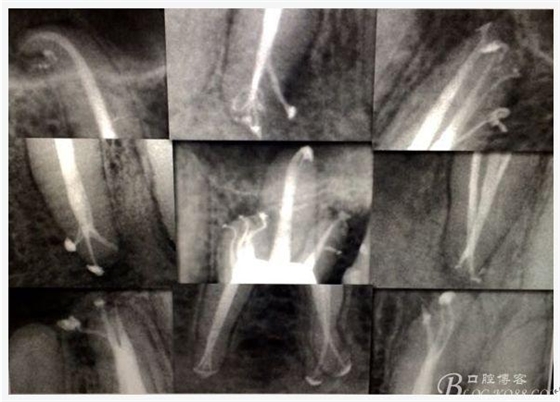

C、牙根的折裂與隱裂 包括橫折,縱折,或者斜折,外傷類的不用討論,主要是某些特殊原因比如牙齒本身結(jié)構(gòu)先天性缺陷再配合后天因素如牙合創(chuàng)傷、咬合平衡發(fā)生改變導(dǎo)致應(yīng)力集中,或者某次瞬間的咬合暴力等一種或者多種因素作用的結(jié)果,具體什么原因這個(gè)要從多方面因素權(quán)衡來(lái)判斷,比如牙齒的松動(dòng)度,詢問(wèn)病史,找不出其它原因時(shí)的重點(diǎn)懷疑,牙齒本事是否處于合應(yīng)力集中的區(qū)域,是否有不良修復(fù)設(shè)計(jì)等等,具體可以通過(guò)臨床“理化檢查(冷熱,叩診等)”再結(jié)合數(shù)值化小牙片,牙髓活力測(cè)定,以及CBCT等來(lái)綜合判斷,重點(diǎn)懷疑牙為上頜的4/5的頰或者腭根,尤其是4或者5的遠(yuǎn)中已是游離缺失或者單端橋等,6的腭根以及下頜的4/5/6都是重點(diǎn)懷疑對(duì)象,而最難診斷的是牙根的隱裂,即使使用CBCT有時(shí)候也沒(méi)辦法確診;

E、X線影像學(xué)的檢查研判能力:這點(diǎn)不需要強(qiáng)調(diào)太多,對(duì)于普通的非CBCT的二維影像對(duì)醫(yī)生讀片能力有一定的要求,有個(gè)逐步提高的過(guò)程,非一蹴而就,需要學(xué)會(huì)把二維的X線影像與三維的解剖結(jié)構(gòu)進(jìn)行良好的對(duì)應(yīng)結(jié)合,對(duì)于某些鈣化的髓室底,應(yīng)通過(guò)想象把根管口的分布、根管的走向以及各種變化通過(guò)想象投射到對(duì)應(yīng)的髓室底上;